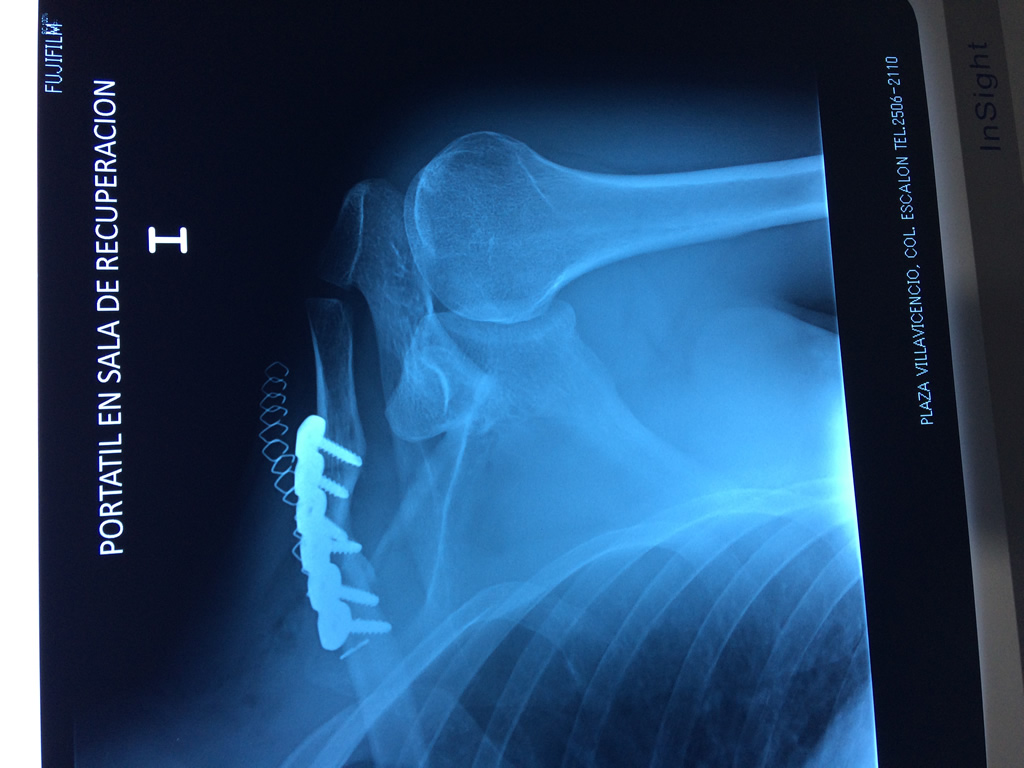

Cirugías de Calcaneo - Clavícula